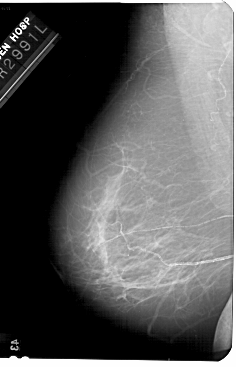

A_1681_1.RIGHT_MLO

RIGHT_MLO LINES 5491 PIXELS_PER_LINE 3226 BITS_PER_PIXEL 12 RESOLUTION 43.5 OVERLAY